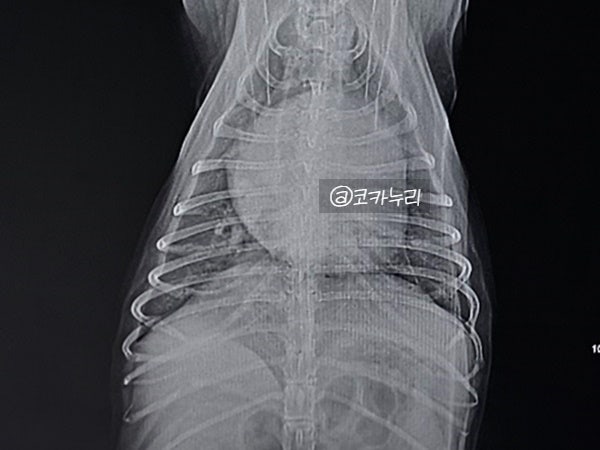

강아지 심장병 증상 기절 실신 응급처치 심폐소생술

강아지 심장병 증상 기절 실신 응급처치 심폐소생술 오늘은 제 반려견 누리가 겪었던 강아지 기절 실신 이...